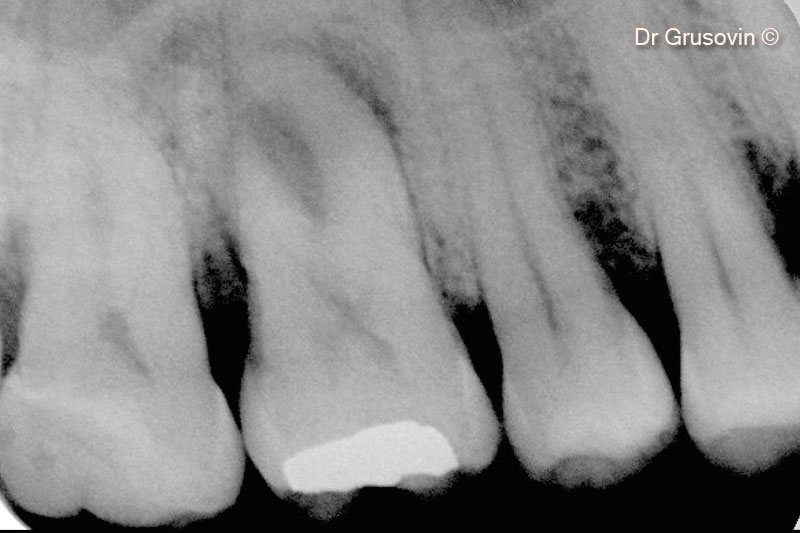

Hình ảnh X-Quang số 16